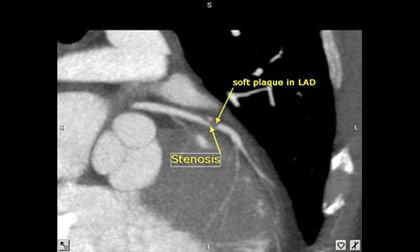

CTA Coronary Artery (Coronary Computed Tomographic Angiography)

การฉีดสีเพื่อตรวจหลอดเลือดหัวใจโดยใช้ MDCT 64 Slices เป็นการตรวจเพื่อค้นหาภาวะหลอดเลือดหัวใจตีบ โดยสามารถบอกระดับความรุนแรงของการตีบของหลอดเลือดที่ไปเลี้ยงกล้ามเนื้อหัวใจได้ หรือใช้ติดตามผลการรักษาในรายที่เคยมีประวัติผ่าตัดหลอดเลือดหัวใจมาก่อน รวมถึงการหาความผิดปกติแต่กำเนิดของหลอดเลือดหัวใจ โดยในปัจจุบันเป็นการตรวจคัดกรองในผู้ป่วยที่มีความเสี่ยง การเตรียมผู้ป่วยที่มีปัจจัยเสี่ยงการเกิดโรคหัวใจ ก่อนทำการผ่าตัดหรือทำหัตถการใหญ่ๆ